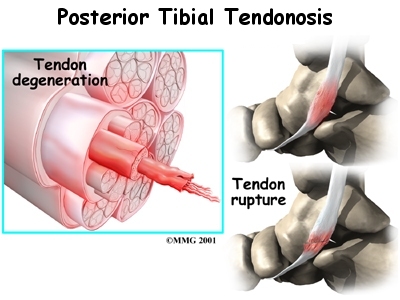

As the tendon heals itself from wear and tear, scar tissue forms, thickening the tendon. This process can continue to the extent that a nodule, or knot, forms within the tendon. Once the painful tendon has changed in structure, the term tendonosis, rather than tendonitis, is used. Unlike with tendonitis, recent evidence shows that inflammation is not present with tendonosis. The area of structural change in the tendon is weaker than normal tendon. The weakened tendon sets the stage for the possibility of rupture of the tendon.

The symptoms of tendonitis of the posterior tibial tendon include pain in the instep area of the foot and swelling along the course of the tendon. In some cases the tendon may rupture due to the degeneration of the tendon. Rupture of the tendon leads to a fairly pronounced flat foot deformity that is easily recognizable. In addition, a patient with a ruptured tendon is unable to rise up very high onto their toes, which also leads to the suspicion of a ruptured tendon.

A badly degenerated or a ruptured tendon may require a tendon graft. Usually, another tendon in the foot, such as the tendon that flexes the four smaller toes (the flexor digitorum longus), is used as a tendon graft to work in place of the posterior tibial tendon.